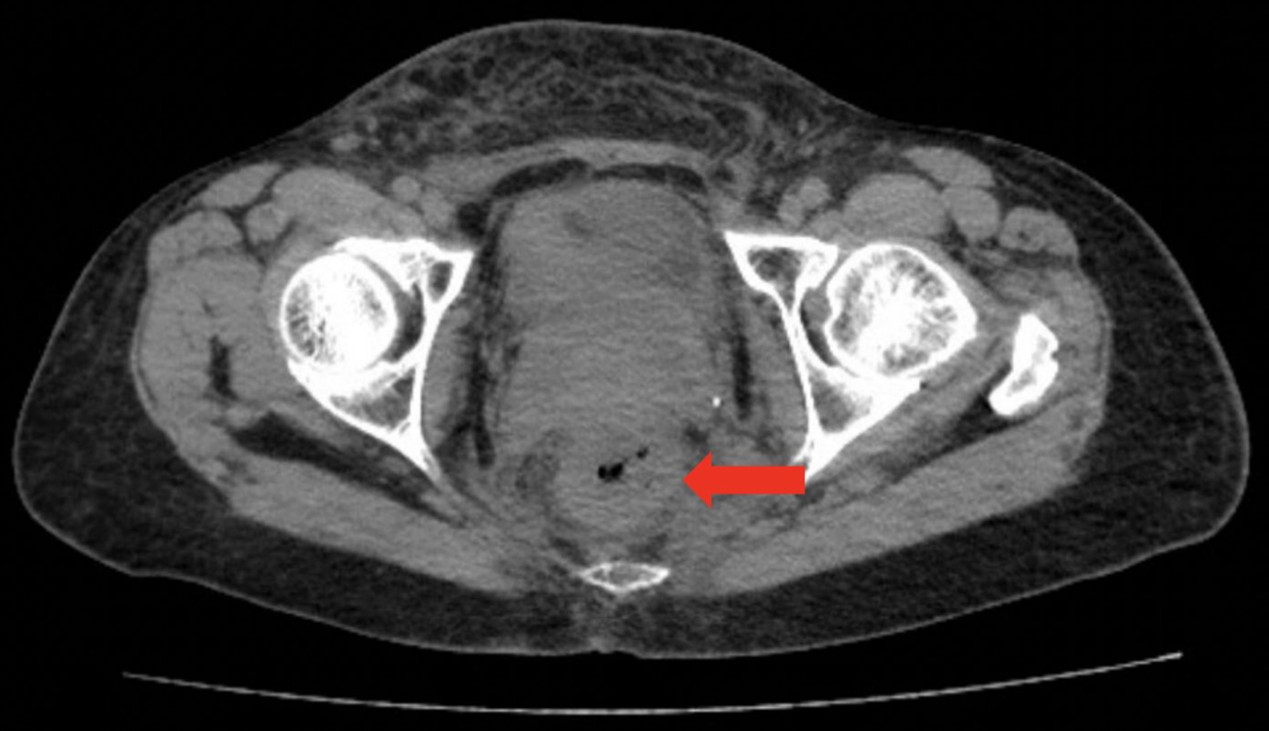

CT检查显示直肠壁增厚(图1),结肠镜检查发现距肛缘12 cm处黏膜改变伴狭窄(图2)。